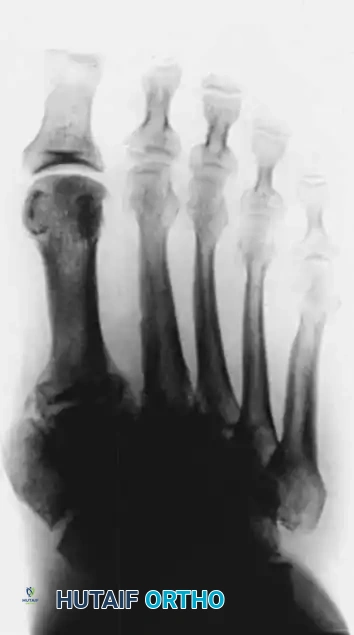

In the presence of motor neuropathy, the intrinsic musculature of the foot atrophies, leading to an intrinsic-minus foot posture. This results in the classic claw toe deformity: hyperextension at the metatarsophalangeal (MTP) joints and flexion at the proximal interphalangeal (PIP) joints. Consequently, the plantar fat pad is drawn distally, leaving the metatarsal heads prominent and unprotected against vertical and shear forces during the terminal stance phase of gait.

• Claw Toe Correction: Correction at the MTP and PIP joints is often necessary. This may involve extensor tendon lengthening, dorsal MTP capsulotomy, and PIP arthroplasty or arthrodesis.

• Metatarsal Head Resection: Resection of one or more prominent metatarsal heads (or a complete pan-metatarsal head resection in severe cases) may be required to relieve plantar pressure and maintain ulcer closure.

FIXED DEFORMITIES IN THE DIABETIC FOOT Surgical Diagram